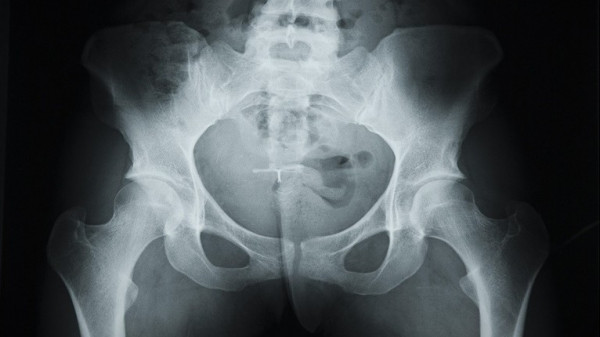

تعرض رجل للسقوط في الشارع ما اضطره لمراجعة المستشفى، وعند إجراء كشف بالأشعة السينية لتحديد مكان الكسر الحاصل في منطقة الحوض، اتضح أن عضوه الذكري تحول إلى عظم.

قرر الأطباء بعد اشتباههم بوجود كسر في حوض رجل (63 سنة) لم يكشف عن اسمه، بعد سقوطه في الشارع، فحصه بالأشعة السينية. ولكن الصور أظهرت عدم وجود أي كسر في عظام الحوض، ولكن عضوه الذكري يتحول تدريجيا إلى عظم، نتيجة تطور الخلايا العظمية فيه، وهذا يحصل عادة نتيجة ظاهرة نادرة جدا سجلت مثلها أقل من 40 حالة في العالم حتى الآن.

ووقعت هذه الحادثة في مدينة نيويورك قبل بضعة أشهر، وبقيت الصور الشعاعية تحت تصرف أطباء المستشفى، ما يسمح بالحديث عن حالة جديدة لما يسمى "التعظم" أي التحول التدريجي لأي عضو في الجسم إلى عظم.

يمكن تشخيص الحالة فقط بواسطة الأشعة السينية، ولعلاجها أو وقف تطورها تستخدم الأدوية المضادة للالتهابات، وعند مراحلها الأخيرة لا بد من التدخل الجراحي.